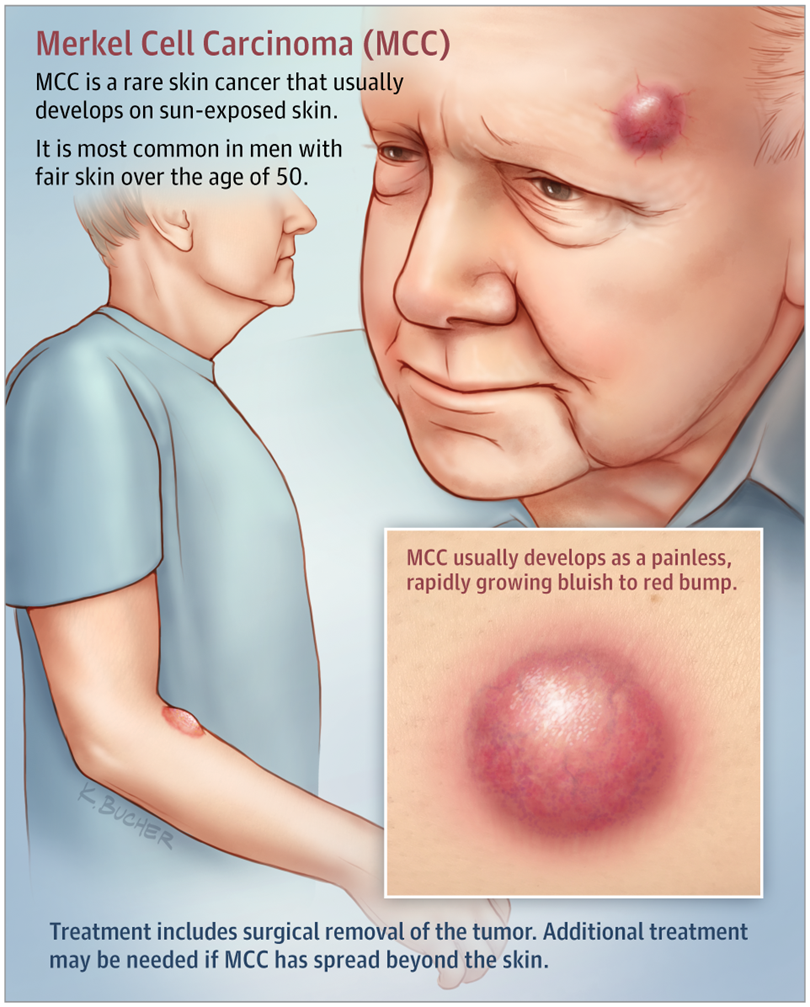

2. Merkel Cell Carcinoma

- Number of People Afflicted Yearly: Worldwide numbers unknown – about 2,000 cases in the U.S. each year

- Area of Body Affected: Skin cancer typically found on the face, head, or neck

- Is it Treatable?: Yes

- Survival Rate: 10-year survival rate of about 57% (about 71% if caught early)

MCC, also known as Merkel Cell Carcinoma, is an extremely uncommon and dangerous form of skin cancer. Skin that is frequently exposed to the sun, such as that seen on the head, neck, and arms, frequently develops MCC.

This type of skin cancer can develop on any part of the body, including locations that are shielded from the sun.

The lump that develops as a result of Merkel cell carcinoma is often painless, solid, and flesh-colored or reddish-purple in color.

It is currently expected that approximately 2,000 persons in the United States receive a diagnosis of Merkel Cell Carcinoma each and every year.

However, a number of publications indicate that there has been a significant rise in the number of instances of MCC during the course of the last ten years.

According to projections made by researchers, the total number of cases of Merkel cell carcinoma in the United States could reach over 2,800 in the year 2020 and 3,250 in the year 2025.